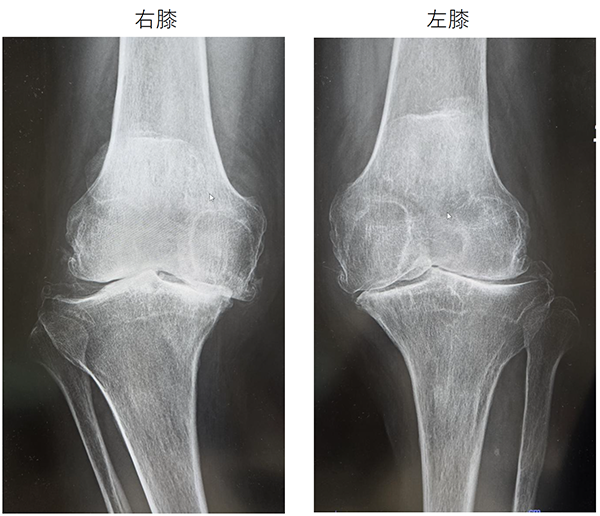

〈手術前のレントゲン〉

右ひざ

左ひざ

〈手術後のレントゲン〉

右TKA後

左TKA後

術前は高度なO脚を呈していましたが、術後は下肢がまっすぐになり、股関節と足関節の中心を結ぶライン(赤線)がひざ関節の中心を通っています。